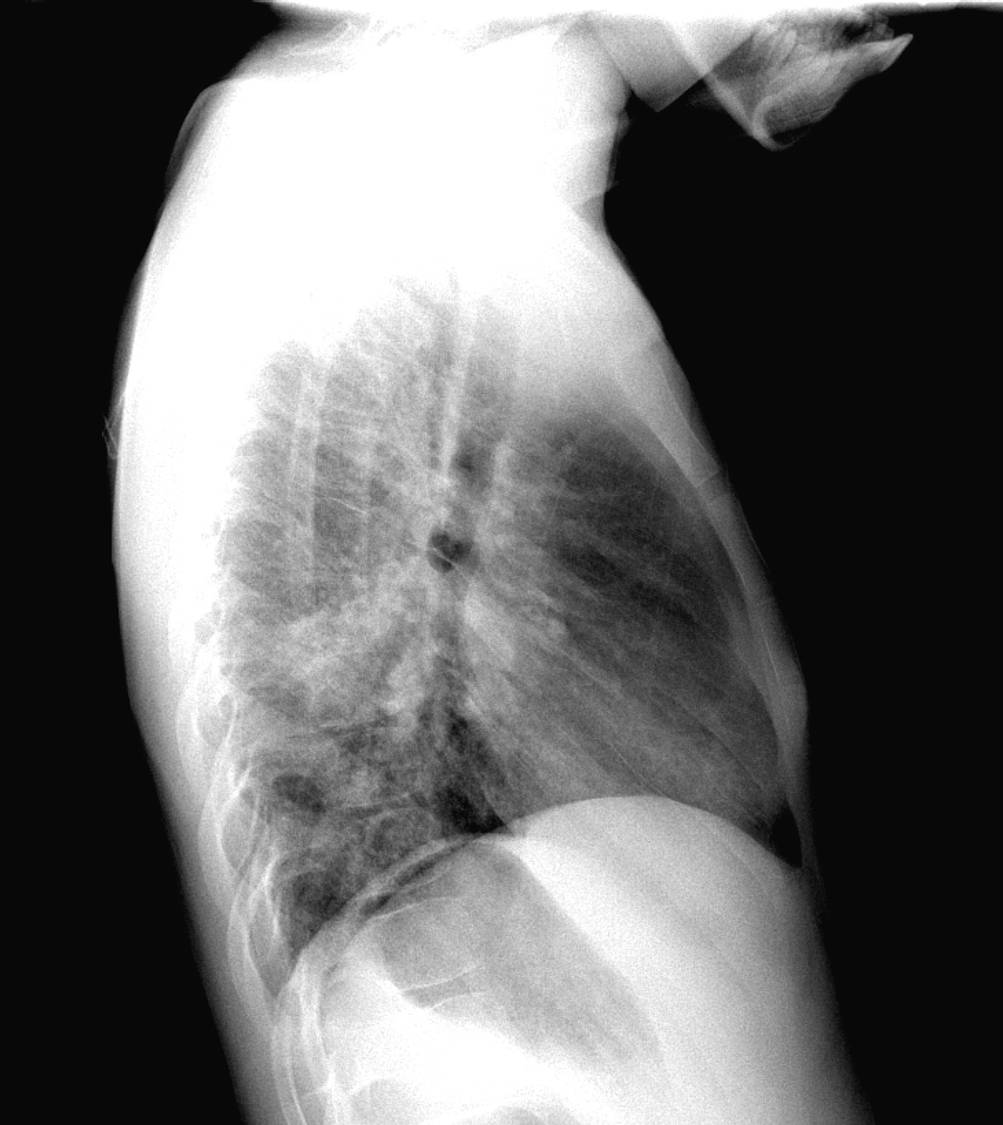

A chest x-ray from local hospital was reviewed

| Figure 1-a | Figure 1-b |